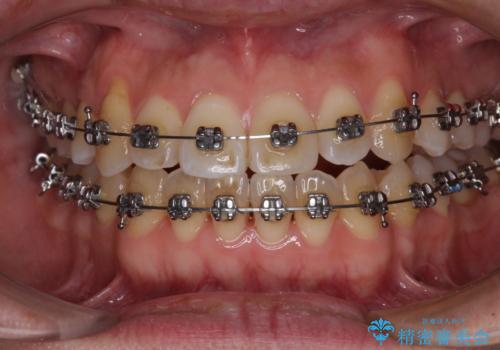

左右の八重歯が気になる ワイヤー装置での咬み合わせ改善

- 矯正装置

- メタルブラケット

- 八重歯と前歯のデコボコを気にして来院された患者様です。

営業職であり、商談などで飲食をする機会が多いとのことで、インビザラインではなく、ワイヤー装置にて矯正治療を行うこととしました。